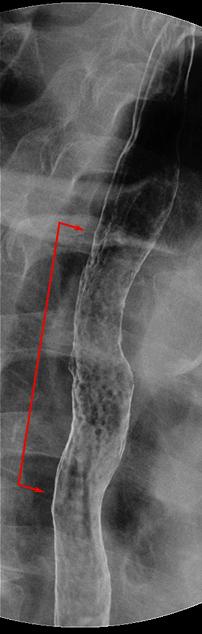

Criteria of Hist.ClassificationMalignant epithelial tumor/Squamous cell carcinoma

LocationEsophagus/Middle third

Technique, MethodX-ray

Macroscopic TypesType 0/IIc (IIc) Superficial depressed type

Size40 -

Depth of Tumor Invasionmucosa